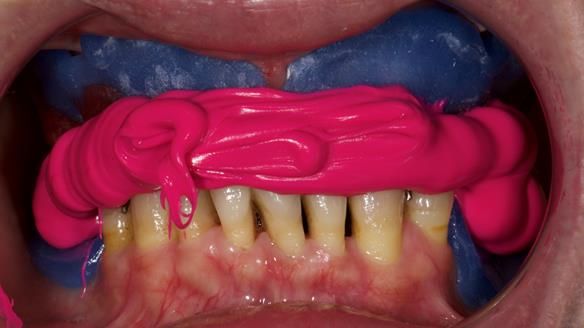

She had previously suffered from generalised periodontitis – stage IV, grade C, currently stable, with reduced attachment across the upper arch.

By the time she came to me, her periodontal condition was stable — but the aesthetics in the upper jaw were very poor.

We provided her with an immediate upper denture (Mk 1), followed by a definitive metal-based upper denture (Mk 2). A lower removable partial denture was discussed, to be made only if needed once the upper treatment was complete. However, at review, this wasn’t necessary — Adnana had excellent neuromuscular control and function, even with a shortened dental arch (SDA).

- Immediate denture (Mk 1) fitted the same day the teeth came out